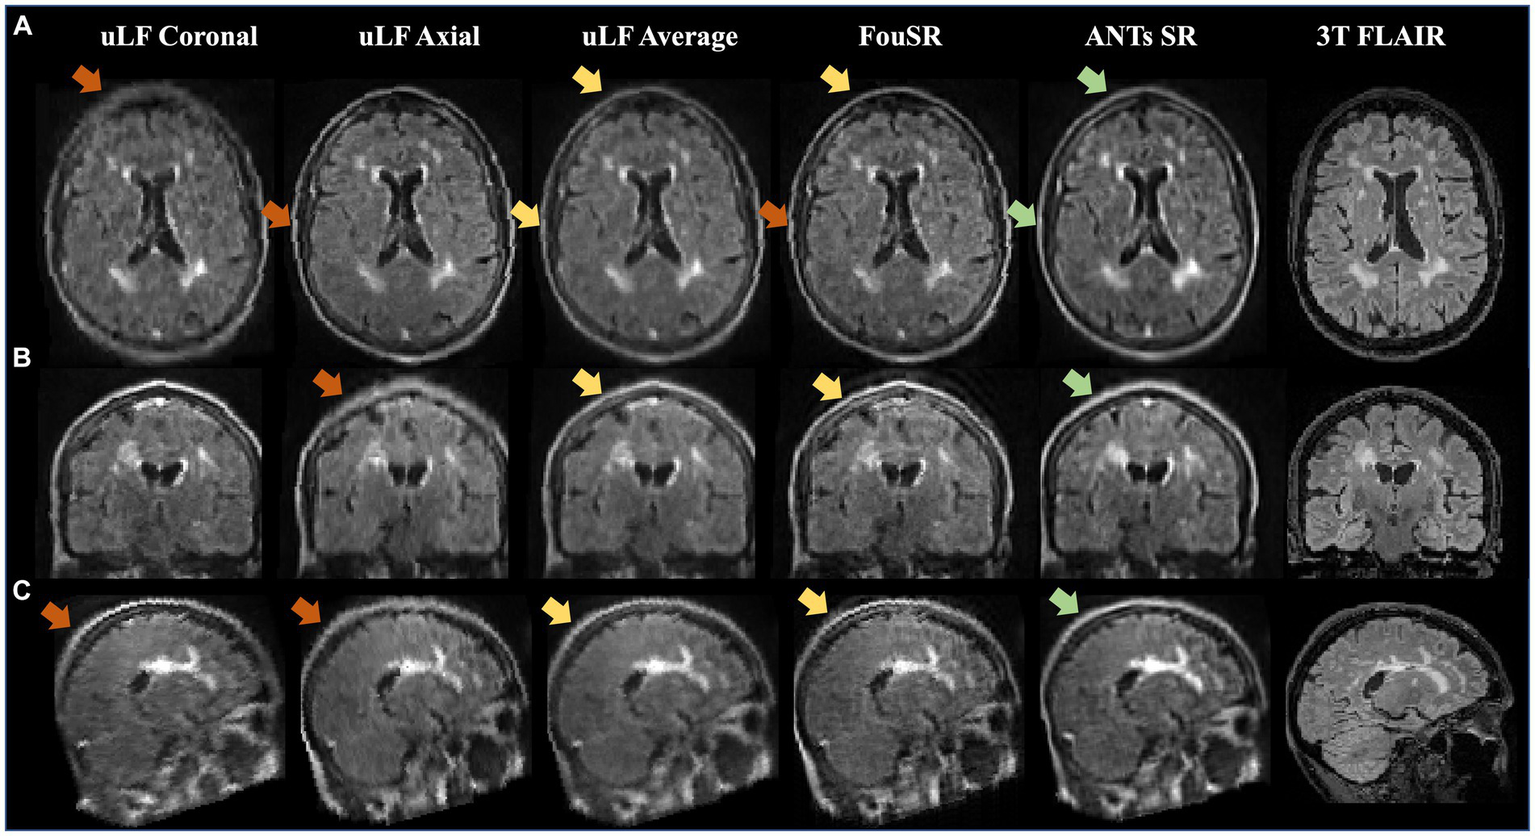

FouSR improves image quality across all three planes. Qualitative visualization of (A) axial, (B) coronal, and (C) sagittal slices in an MS case with high lesion burden in ULF FLAIR images, the average of ULF FLAIR images, after FouSR algorithm and after ANTs SR algorithm is shown. Arrows point to artifacts from partial voluming along the slice direction that is seen in the coronal and axial ULF (orange arrows) but reduced in FouSR and average images (yellow arrows) and absent in ANTs-SR images (green arrows).

Figure 5 presents an example of a participant with a high lesion burden. Notably, FouSR in Figure 5, column 3, shows enhanced resolution across all three axes, surpassing the through-plane resolution of the ULF coronal and ULF axial scans, suggesting the recovery of information from the in-plane voxels of the ULF coronal (Figure 5, column 1) and ULF axial images (Figure 5A, column 2). FouSR demonstrated improved image quality relative to the ULF coronal and ULF axial images in the slice direction. ULF average and ANTs displayed more pronounced blurring along lesion edges and sulci than the FouSR approach. Importantly, certain artifacts visible in the ULF coronal and axial images (Figure 5C, arrows) were consistently retained in the FouSR and ANTs-SR images, although they exhibited reduced visibility in the ULF average. Additionally, ringing artifacts were introduced in FouSR (Figure 5C, box), which were not visible in other scans.